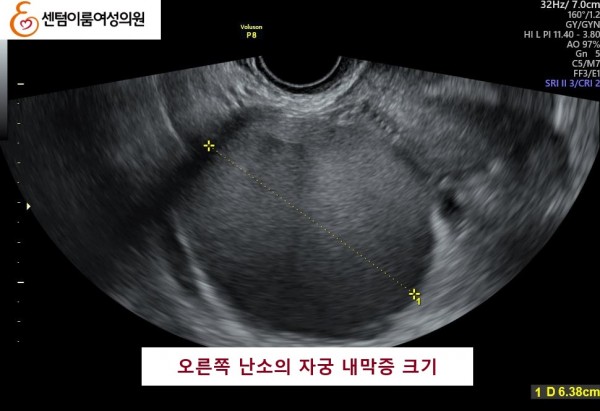

2024.12월 본원 내원시 오른쪽 난소에 자궁 내막증이 있었고, 자궁 내막 또한 얇았습니다.

오른쪽 난소 알콜 경화술을 통하여 내막증을 치료 후, 자연 임신에 성공 하셨습니다.